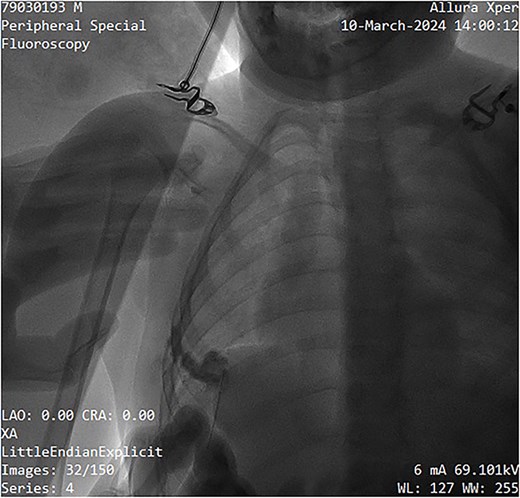

The sclerosing agent used was 3% polidocanol foam, prepared via Tessari’s technique. The foam formulation comprised 3 ml of polidocanol, 3 ml of normal saline, and 3 ml of air, totaling 9 ml. The non-radiopaque polidocanol was administered through the same needle. The contrast was subsequently ``washed out'' by the sclerosing agent, ensuring comprehensive treatment of all cystic spaces (Fig. 4). The procedure was done as a day case under local anesthesia with a support staff calming the patient. Pre- and post-procedure digital subtraction angiography images were obtained for mapping and completion. Post-instillation ultrasonography was performed to confirm adequate sclerotherapy distribution and to confirm extravasation did not occur. Compression taping was applied post-procedure, and the patient was discharged within a few hours on oral paracetamol as required.

Image showing sclerotherapy administration through the same needle used for contrast injection, effectively ``washing out'' the contrast while sclerosing the venous malformation.